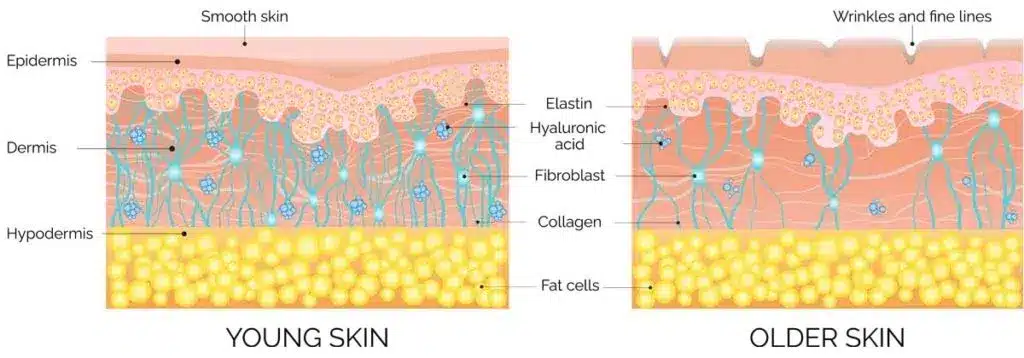

- Facial volume loss is a natural aging process, leading to a sunken appearance in cheeks, temples, and jawline.

- Collagen production decreases over time, resulting in reduced skin elasticity, wrinkles, and roughness.

Collagen

Collagen is crucial for skin health, and its decreased production leads to signs of aging, including facial volume loss and hollow areas, which contribute to an aged appearance.

- Facial volume loss is a natural aging process, leading to a sunken appearance in cheeks, temples, and jawline.

- Collagen production decreases over time, resulting in reduced skin elasticity, wrinkles, and roughness.

What is Collagen?

Collagen is crucial for skin health, and its decreased production leads to signs of aging, including facial volume loss and hollow areas, which contribute to an aged appearance.

This treatment provides immediate volume and continues to work over time by stimulating your body’s natural collagen production. This leads to natural-looking improvements in your facial volume and shape. The procedure is done with precision, and multiple sessions might be recommended for the best results. As collagen production increases, you’ll notice more improvements.

Saggy skin can be caused by a combination of factors, including natural aging, genetics, and lifestyle choices. The loss of collagen and elastin in the skin, as well as decreased muscle tone, can contribute to the appearance of sagging. Factors such as sun exposure, smoking, and poor nutrition can also accelerate the process of sagging skin.